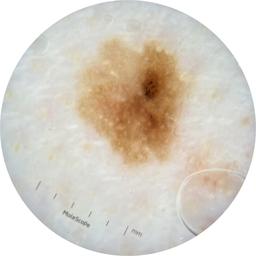

ISIC_3055924

acquisition_day 491

age_approx 80

anatom_site_1 Trunk

anatom_site_2 Posterior trunk

anatom_site_general posterior torso

concomitant_biopsy False

diagnosis_1 Benign

diagnosis_confirm_type single image expert consensus

family_hx_mm False

image_type dermoscopic

personal_hx_mm True

sex male